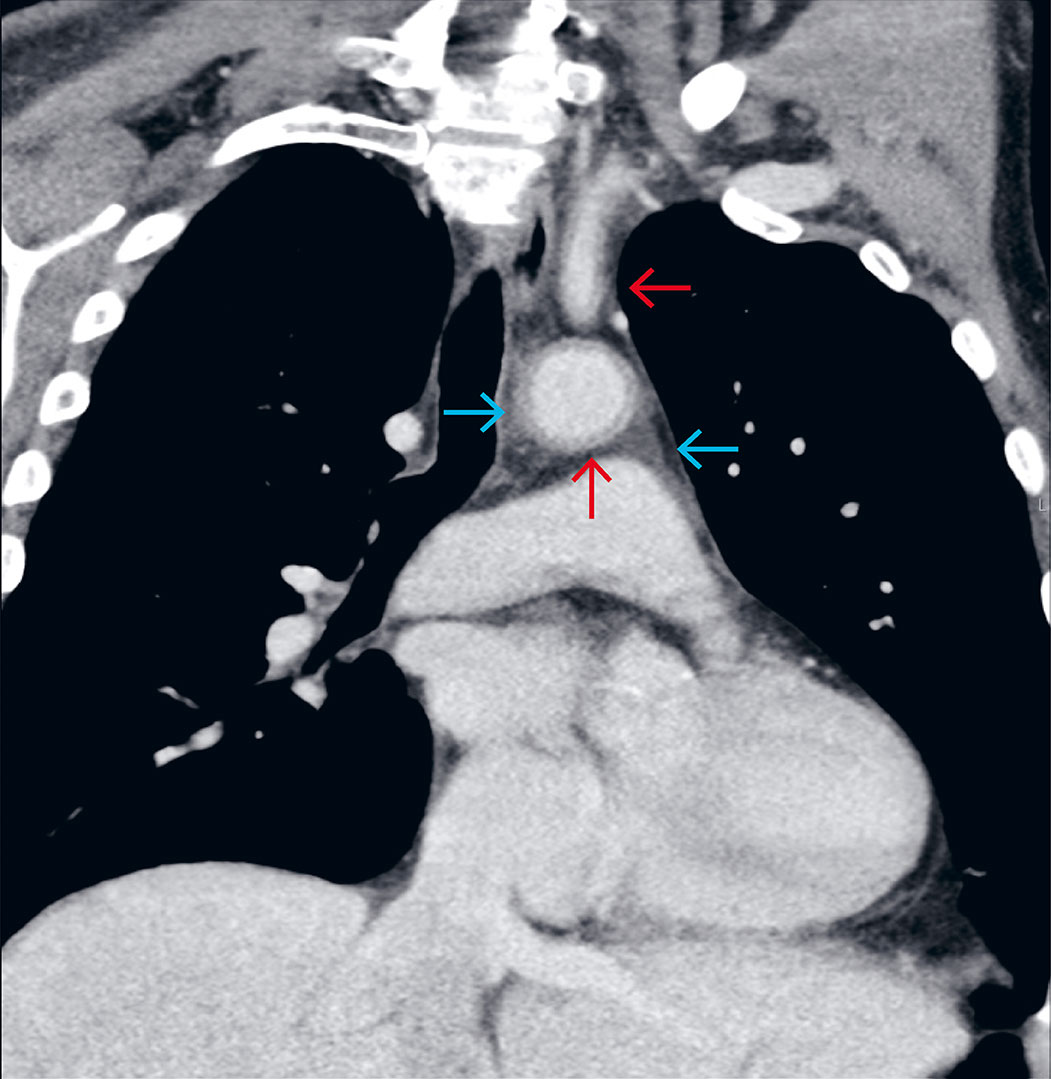

På grunn av manglende behandlingsrespons etter tre dager, ble antibiotika endret til intravenøs cefotaksim 2 g × 3 i kombinasjon med metronidazol 1,5 g × 1. På fjerde dag endret man igjen til intravenøs meropenem 1 g × 3 og vankomycin 1 g × 2. CRP-nivået hadde da steget til 331, og pasienten hadde fremdeles febertopper > 38,7 °C. Han rapporterte nå også om lettgradige brystsmerter, og ble vurdert som påfallende lite infeksjonspreget. Alle dyrkninger var negative, røntgen toraks var normalt og transtorakal ekkokardiografi viste ikke tegn til endokarditt. På fjerde dag ble det også gjort computertomografi (CT) med kontrastmiddel i portovenøs fase av toraks, abdomen og bekken som ledet til riktig diagnose. CT-undersøkelsen viste nemlig vaskulittforandringer i aorta og flere avgangskar (figur 1). G-CSF-utløst aortitt ble vurdert som sannsynlig diagnose, og etter en tverrfaglig diskusjon ble det startet peroral behandling med prednisolon 40 mg × 1. De neste dagene ble pasienten afebril, og CRP-nivået falt markant. Antibiotika ble seponert etter sju dager, og pasienten ble utskrevet i velbefinnende etter ti dager. Prednisolon ble trappet ned og seponert i løpet av tre måneder. Lymfomet ble vellykket behandlet med fire R-CHOP-kurer, etterfulgt av to kurer med kun rituksimab. Granulocyttkolonistimulerende faktor ble ikke gitt igjen etter første kur. To år etter behandlingsstart var det fremdeles ingen tegn til residiv av lymfom eller vaskulitt.

Bildediagnostikk er avgjørende for å kunne stille diagnosen og hindre unødvendig antibiotikabehandling. Det var til slutt CT-undersøkelsen med kontrastmiddel i portovenøs fase som ledet oss til riktig diagnose. For målrettet utredning eller oppfølging av ekstrakraniell vaskulitt er positronemisjonstomografi med integrert CT